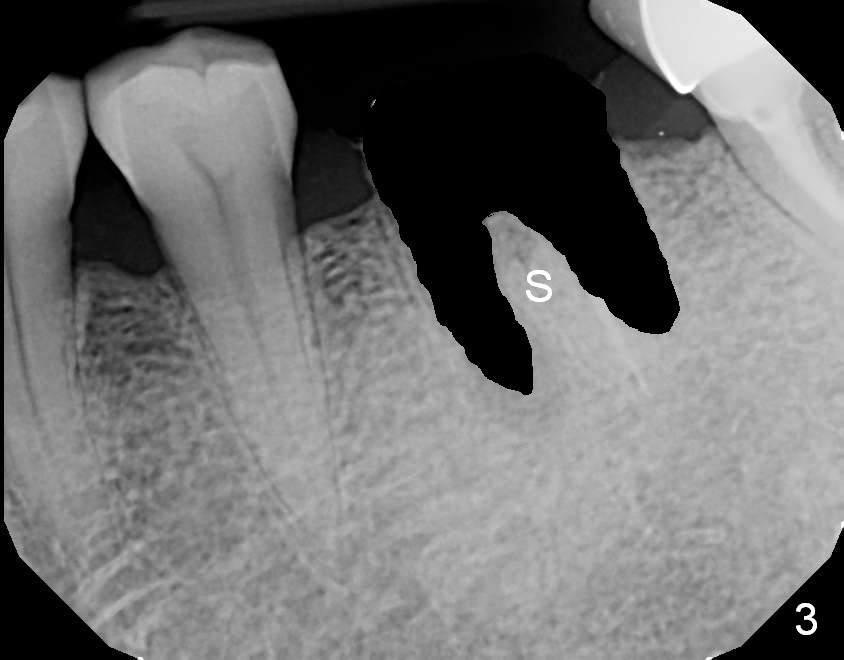

A 69-year-old man has pain in the tooth #19 (Fig.1). When a rubber dam clamp is placed for retreatment, the crown falls out (Fig2). Due to short clinical crown, the tooth is deemed non-salvageable. Fig.3 is an illustration after extraction. It seems that the septum is wide at the base. Measure socket depth. An osteotomy will be 1 mm longer than the socket depth (Fig.4). The osteotomy is initiated in the middle of the septum 14 mm deep. Insert a shortest parallel pin for occlusal check and a 14 mm long parallel pin for X-ray. Change trajectory if needed. A 5x14 mm tissue-level implant or 12 mm bone-level implant will be placed to prove that a short implant can achieve primary stability mainly by engagement into the septal struts and ~ 1 mm into apical new bone. With 2 roots distally, the position of the immediate implant will be affected?